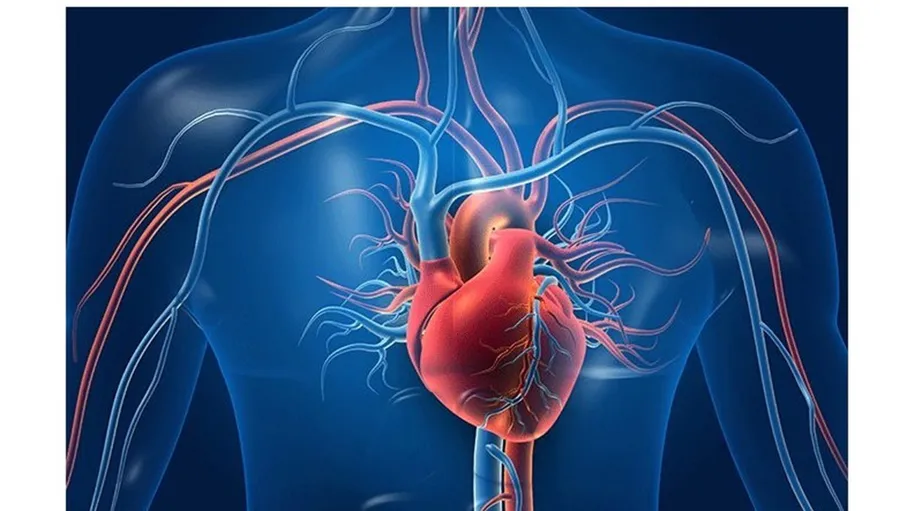

يشير الدكتور ألكسندر مياسنيكوف إلى أنه من شأن الأدوية المستخدمة في خفض مستوى ضغط الدم مساعدة القلب، ولكن هذا لا يحصل دائما.

نصائح لمن يعاني من ارتفاع مستوى ضغط الدم

ووفقا له، يمكن للأدوية التي توضع تحت اللسان لخفض مستوى ضغط الدم بسرعة أن تقتل الشخص لأنها تخفض مستوى ضغط الدم بسرعة ليس في الشرايين فقط، بل وأيضا في الكلى والرئتين والدماغ والقلب، ما يؤدي إلى الإصابة باحتشاء عضلة القلب والجلطة الدماغية والقصور الكلوي الحاد. لذلك، لا ينصح بخفض مستوى ضغط الدم بسرعة.

وينصح مياسنيكوف باستخدام هذه الأدوية في حالات ارتفاع مستوى ضغط الدم الحاد فقط بحضور طبيب الإسعاف لأنه إذا حدث أي شيء، فسوف يتخذ بسرعة ما ينبغي من الإجراءات إذا تطلب الأمر لكي لا يعاني المريض من أي مضاعفات. فيستي. رو